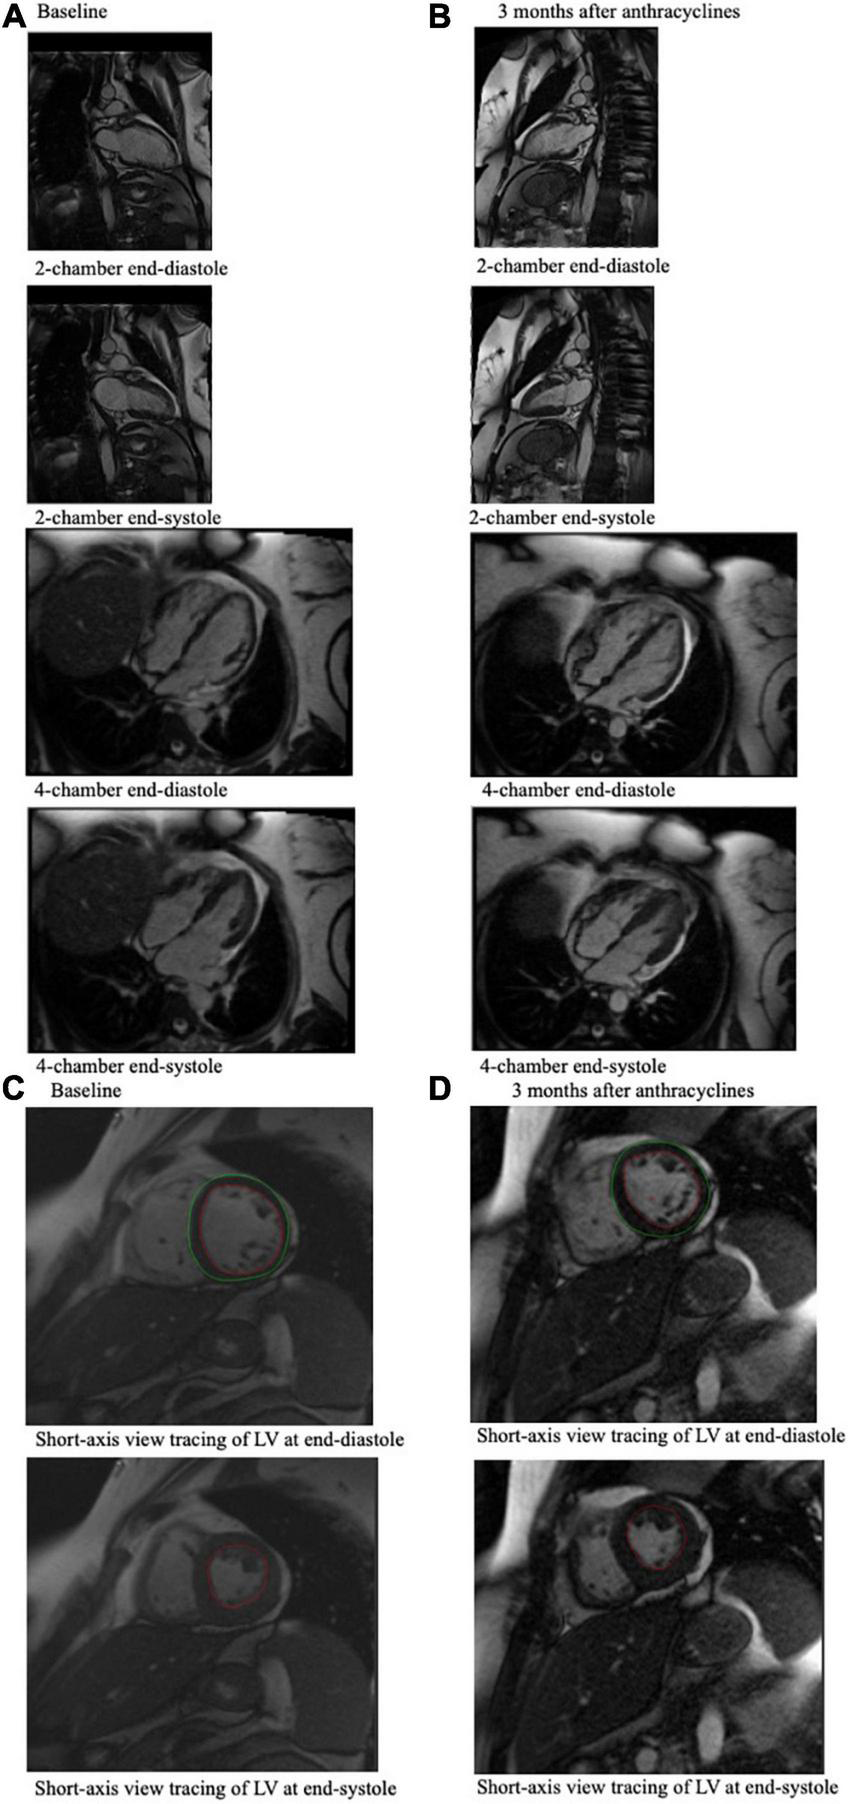

Furthermore, a study by Melendez et al. (21) used CMR to determine that among 112 cancer patients (72% of whom received anthracyclines), 26 patients developed significant declines in LVEF of > 10% or to values < 50% at 3 months (21). Among these 26 patients, 19% were determined to have a decline in LVEF due to a decline in LVEDV, whereas 60% were determined to have a decline in LVEF due to an increase in LVESV. Systolic heart failure is associated with LVEF drops given by LVESV changes, but changes in LVEDV may be due to volume depletion, which is a common occurrence in cancer patients. Thus, the LVEF may decrease due to a decline in LVEDV or an increase in LVESV, and CMR allows for clinical determination of which case is present in a patient (Figure 2).

FIGURE 2

CMR end-diastole and end-systole frames from a cine loop for a 49-year-old breast cancer patient who experienced an associated LVEF decline from 61% at baseline (A) to 43% 3 months after anthracycline-based chemotherapy (B), which was measured using these CMR images. (A) Shows 4-chamber and 2-chamber view CMR imaging of the cancer patient pre-chemotherapy, and (B) shows CMR imaging of the same cancer patient 3 months after chemotherapy. (C) Shows the short-axis view tracing of the LV at end-diastole and at end-systole at baseline, which can be compared to (D) which shows short-axis view tracings of the LV at end-diastole and end-systole of this patient at 3 months after chemotherapy. In these tracings, the red tracing outlines the blood pool in the left ventricle, and the green tracing outlines the left ventricle. These tracings, which indicate LVEDV and LVESV, are used to calculate LVEF.